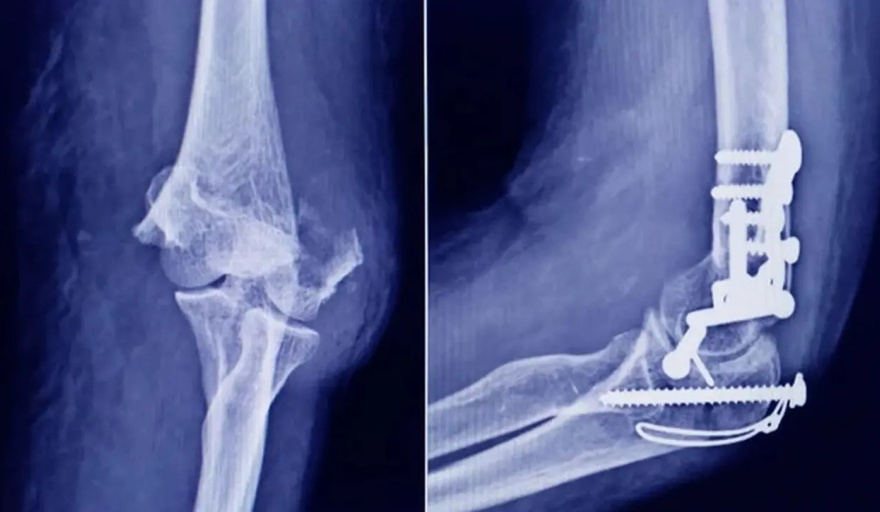

La Administración Nacional de Medicamentos, Alimentos y Tecnología Médica (ANMAT) emitió una alerta sanitaria tras detectar la circulación de un tornillo traumatológico falsificado que podría generar serias complicaciones en pacientes sometidos a cirugías ortopédicas.

El hallazgo se produjo durante una inspección de control de mercado en una ortopedia de la ciudad de San Miguel de Tucumán. Allí se detectó una unidad que imitaba un producto original de la empresa Stryker Corporation, correspondiente al tornillo registrado bajo el número PM 594-139, de 10 mm por 28 mm.

Tras el secuestro de la muestra, el organismo presentó el producto ante la responsable técnica de la firma, quien confirmó que se trataba de una falsificación. Según informó ANMAT, el tornillo no cumple con los estándares de seguridad ni con las características del producto original, lo que representa un riesgo directo para la salud de los pacientes.

Entre las principales diferencias detectadas, se destacó que el tornillo auténtico de Stryker cuenta con fecha de vencimiento, dato que no figura en la unidad falsificada. Además, la empresa nunca utilizó envases tipo pouch de la marca 3M para este producto, otro indicio que permitió identificar la irregularidad.

También se detectaron diferencias en el método de esterilización. Mientras que el tornillo original se esteriliza mediante Radiación Gama, la unidad falsificada habría sido sometida a esterilización por vapor o formaldehído. A esto se suma una diferencia visible en el color del implante: el original presenta un tono gris opaco, mientras que el falso es incoloro y puede observarse a través del envase transparente.